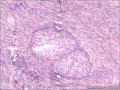

卵巢里边这两团是什么、?巧克力囊肿吗?伴黄体血肿吗?组织中的腺体是子宫内膜腺体吗

• 卵巢里边这两团是什么、?巧克力囊肿吗?伴黄体血肿吗?组织中的腺体是子宫内膜腺体吗图2

图2

图1-5,Brenner细胞巢。6,黄体,是不是血肿,要看多大吧。7-10是子宫内膜异位囊肿。11,确定也是卵巢吗?

6,黄体囊肿,1.5cm。

7-10是子宫内膜异位囊肿

图片较复杂,包含的病变有Brenner细胞巢,黄体囊肿及子宫内膜异位囊肿